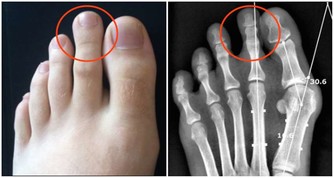

3、Playstation 拇指(Playstation Thumb)